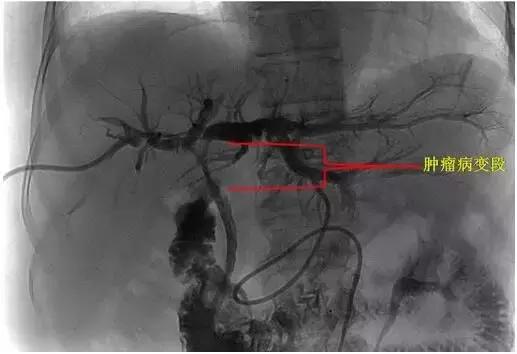

术中DSA下示意图:

1、 肿瘤病变狭窄段

2、插入射频消融导管

3、射频消融治疗及支架置入后造影再通